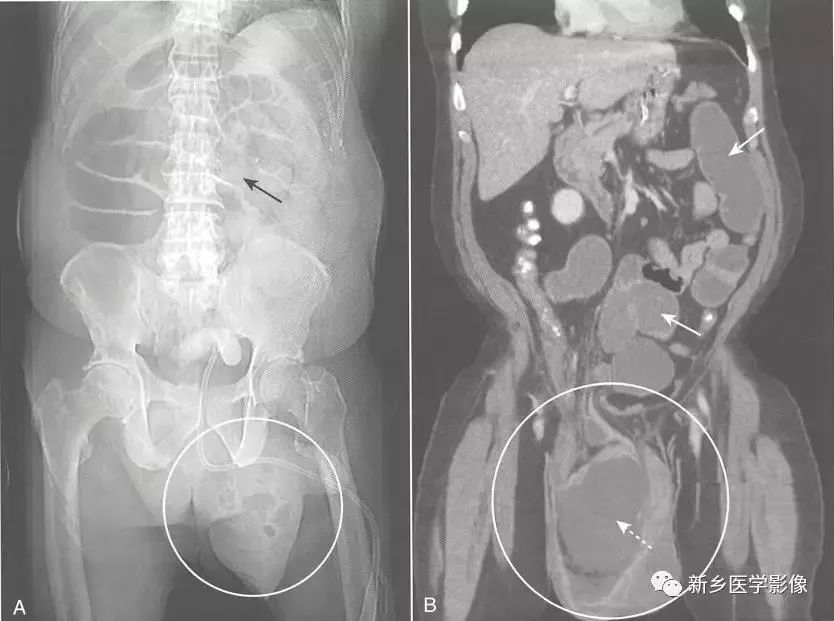

机械性肠梗阻

肠梗阻CT

肠梗阻平片